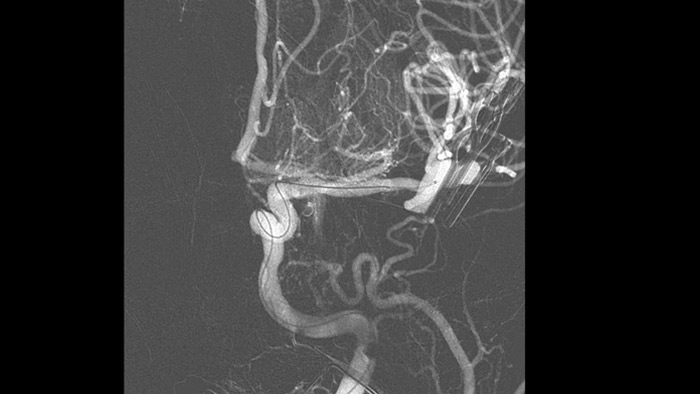

SmartCT Angio est une technique d’acquisition à rayons X qui génère une visualisation 3D haute résolution complète des vaisseaux cérébraux à partir d’une seule séquence d’angiographie rotationnelle, contrôlée via l’écran tactile de la table. Cela améliore la visibilité d’une anatomie tortueuse ou complexe qui n’est pas visible sur une image 2D ou d’angiographie par soustraction numérique (ASN).

SmartCT Angio fournit une vue volumétrique en quelques secondes pour faciliter l’évaluation de l’emplacement, de la taille, du cou et de la gravité de l’anévrisme pour la planification du traitement. Les volumes 3D sont visualisés avec une résolution spatiale élevée et une compensation automatique des mouvements du patient.